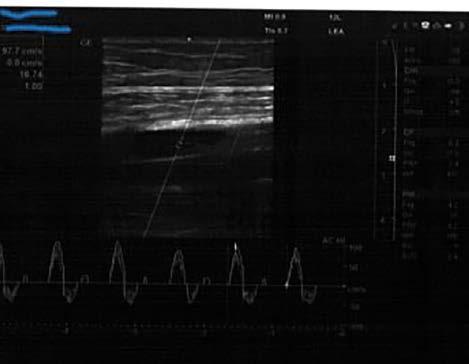

Pseudomonas aeruginosa is recognised as an opportunistic pathogen and a common contributor to wound infections. This study focused on evaluating the antibacterial activity of selected Polish honeys against P. aeruginosa. Six bacterial strains isolated from wounds and 4 types of honeys (multifloral, linden, buckwheat, and heather) were utilised. The minimal inhibitory concentrations (MIC) were determined through the micro-dilution method employing 96-well plates, while antibiofilm activity was assessed using fluorescence microscopy after a 4-hour incubation period with the honeys. The results indicated diverse antibacterial efficacy among honeys, with linden and heather honeys demonstrating the most potent activity. Linden honey displayed an average MIC

of 20.8%, while heather honey exhibited an MIC of 25%. Both honeys significantly reduced biofilm formation, with linden honey achieving a reduction of 54–67% and heather honey of 45-58%. Buckwheat and multifloral honeys exhibited lower activity, demonstrating average MIC levels of 37.5% and 41.7%, respectively, and a biofilm reduction below 20%. Conclusively, Polish honeys exhibited promising activity against both planktonic and biofilm forms of P. aeruginosa. These findings suggest potential applications in wound healing treatments, emphasising the need for further research in this area. The study contributes valuable insights to the limited literature on the antibacterial activity of Polish honeys.

Minimal Inhibitory Concentrations

The minimal inhibitory concentrations (MIC) of the honeys were determined using the micro-dilution method with 96-well plates (Nest Scientific Biotechnology, China). The experimental procedures followed the methodology outlined in our previous publications [17, 18]. In summary, each well received 90 µl of Mueller Hinton broth (Graso Biotech, Poland) and 10 µl of bacterial suspension, resulting in a final inoculum concentration of 105 CFU/ml, as per McFarland standards. Serial dilutions of honey were carried out during the course of the study. The plates were then incubated at 37°C for 24 hours, and MIC values were determined through visual analysis.

Anti-biofilm activity test

Biofilm formation occurred in 12-well plates with Mueller Hinton broth over 48 hours at 37°C. After incubation, the wells were rinsed with PBS, and 1 mL of 50% honey water solution was introduced for 4 hours. Following this, the plates underwent three PBS washes. The assessment of anti-biofilm activity was conducted using the LIVE/DEAD BacLight Bacterial Viability Kit (Invitrogen, USA), following the manufacturer’s

instructions. The results were observed using a fluorescence microscope Leica DM 1000 LED fluorescence microscope (Leica, Germany) with a Progres Gryphax camera (Jenoptik, Germany). The acquired images were analysed using Fiji, a distribution of the image analysis program ImageJ [19]. The program was employed to calculate the number of bacterial cells within the biofilm following the action of the honeys.

Results

the research demonstrated varied antibacterial activity among the honeys. In terms of minimum inhibitory concentration (MIC), the most effective activity was exhibited by linden and heather honey, with MICs at average levels of 20.8% and 25%, respectively (Table I). Buckwheat and multifloral honeys showed weaker activity, with average MIC levels of 37.5% and 41.7%, respectively.

Similarly to MIC results, superior effectiveness of linden and heather honeys was observed in the assessment of antibiofilm activity. Linden honey led to a reduction in biofilm by 54–67% after 4 hours of exposure, while heather honey showed a reduction at the level of 45–58%. Buckwheat and multifloral honeys exhibited much weaker antibiofilm effects, with their biofilm reduction below 20% (Figure 1).